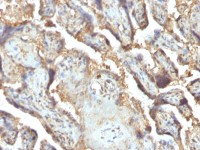

Phosphatase orphan 2 antibody [N1C3] detects Phosphatase orphan 2 protein at cytoplasm in human endometrial cancer by immunohistochemical analysis.

Sample: Paraffin-embedded human endometrial cancer.

Phosphatase orphan 2 antibody [N1C3] (GTX119798) diluted at 1:500.

Antigen Retrieval: Citrate buffer, pH 6.0, 15 min